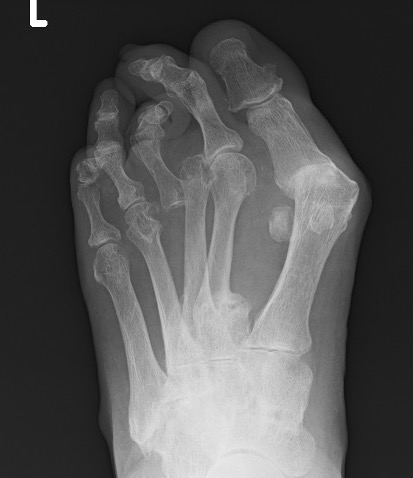

Forefoot

Great toe

Hallux valgus / rigidus

Metatarsalgia

Pathology

Synovitis of MTPJ with capsular destruction

- dorsal subluxation MTPJ

- claw toes develop (MTPJ hyperextended, PIPJ flexed)

- plantar fat pad displaced distally and metatarsal heads exposed to plantar skin